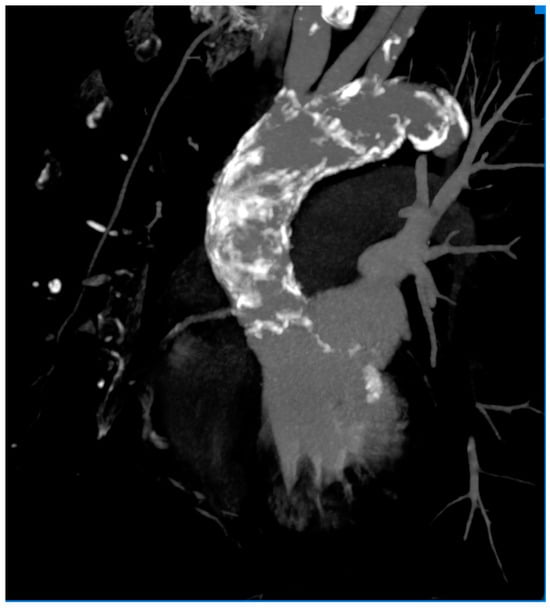

2. Case Report

3.2. Coronary Artery Disease